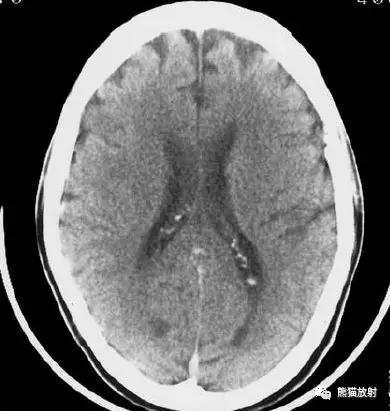

右侧大脑中动脉区域梗死的典型演变:

a)急性期

b)早期亚急性期(2天,从临床起病开始)

c)亚急性晚期(2周后)

d)慢性期(一年后)